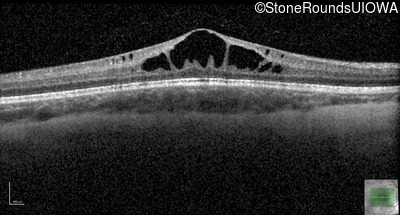

Optical Coherence Tomography - Left - 20/40

Exemplar / OCT Stack